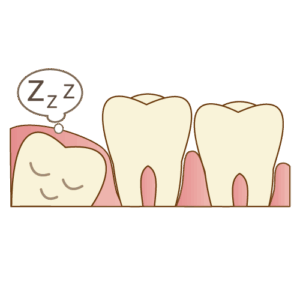

親知らずは、なんと“歯の中でいちばん奥の奥”にいる 第三大臼歯(だいさんだいきゅうし) のこと!

最大4本ありますが、

「生えてこない人」

「そもそも親知らずがない人」

…なんてこともあるんです。

あごのスペースが足りないと、ちょっと窮屈に生えてきてしまい、

横向きになったり、半分だけ顔を出したりと、個性的な生え方をするのが特徴です。

親知らずはいつ生えるの?タイミングはひとそれぞれ!

親知らずが生え始める時期はかなりバラバラ!

一般的には 18〜25歳頃 に出てくることが多いですが、早い人もいれば遅い人もいます。

まっすぐきれいに生えている

-

きちんと磨けている

トラブルなし

将来、歯の移植に使える可能性がある